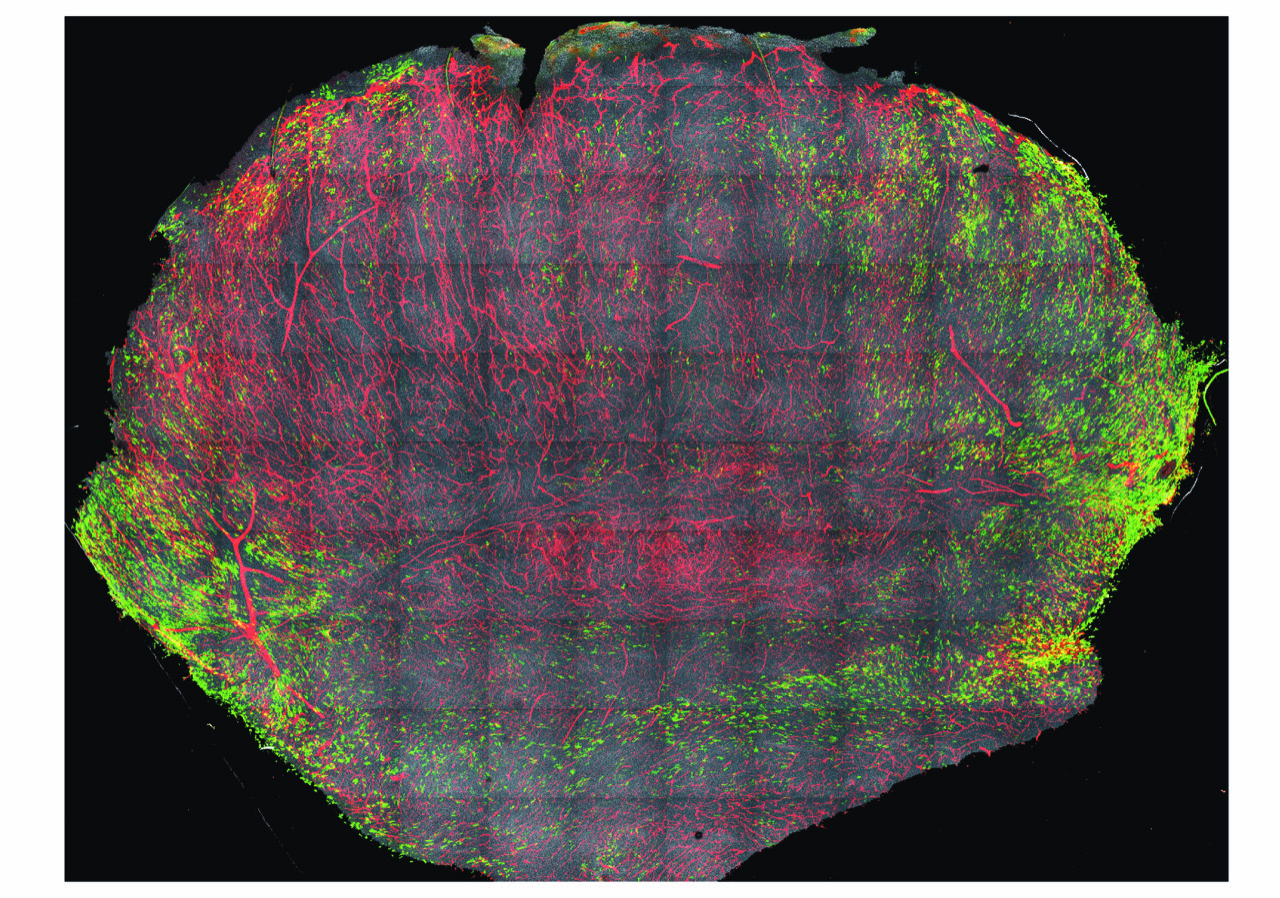

Une équipe de l’Institut Curie, de l’Inserm et du CNRS1  a mis en lumière un nouveau mécanisme moléculaire, jusqu’alors inconnu, liant les œstrogènes (hormones sexuelles féminines) à l’aggravation de certains cancers non classiquement considérés comme hormono-dépendants, tels que le mélanome, le cancer gastrique ou encore le cancer de la thyroïde. Ces travaux, publiés dans Nature le 11 juin 2025, ouvrent la voie à de nouvelles stratégies thérapeutiques, en particulier pour les femmes en âge de procréer.

• 1Ces travaux ont été menés par le Dr Lionel Larue, directeur de recherche à l’Inserm, chef de l’équipe Développement normal et pathologique des mélanocytes dans l’unité Signalisation, radiobiologie et cancer (Institut Curie, Inserm, CNRS, Université Paris Saclay) et le Dr Véronique Delmas, directrice de recherche au CNRS dans la même équipe.

Targeting GRPR for sex hormone-dependent cancer after loss of E-cadherin. Jérémy H. Raymond, Zackie Aktary, Marie Pouteaux, Valérie Petit, Flavie Luciani, Maria Wehbe, Patrick Gizzi, Claire Bourban, Didier Decaudin, Fariba Nemati, Igor Martianov, Irwin Davidson, Catherine-Laure Tomasetto, Richard M. White, Florence-Mahuteau Betzer, Béatrice Vergier, Lionel Larue*, et Véronique Delmas*. Nature, 11 juin 2025, https://doi.org/10.1038/s41586-025-09111-x